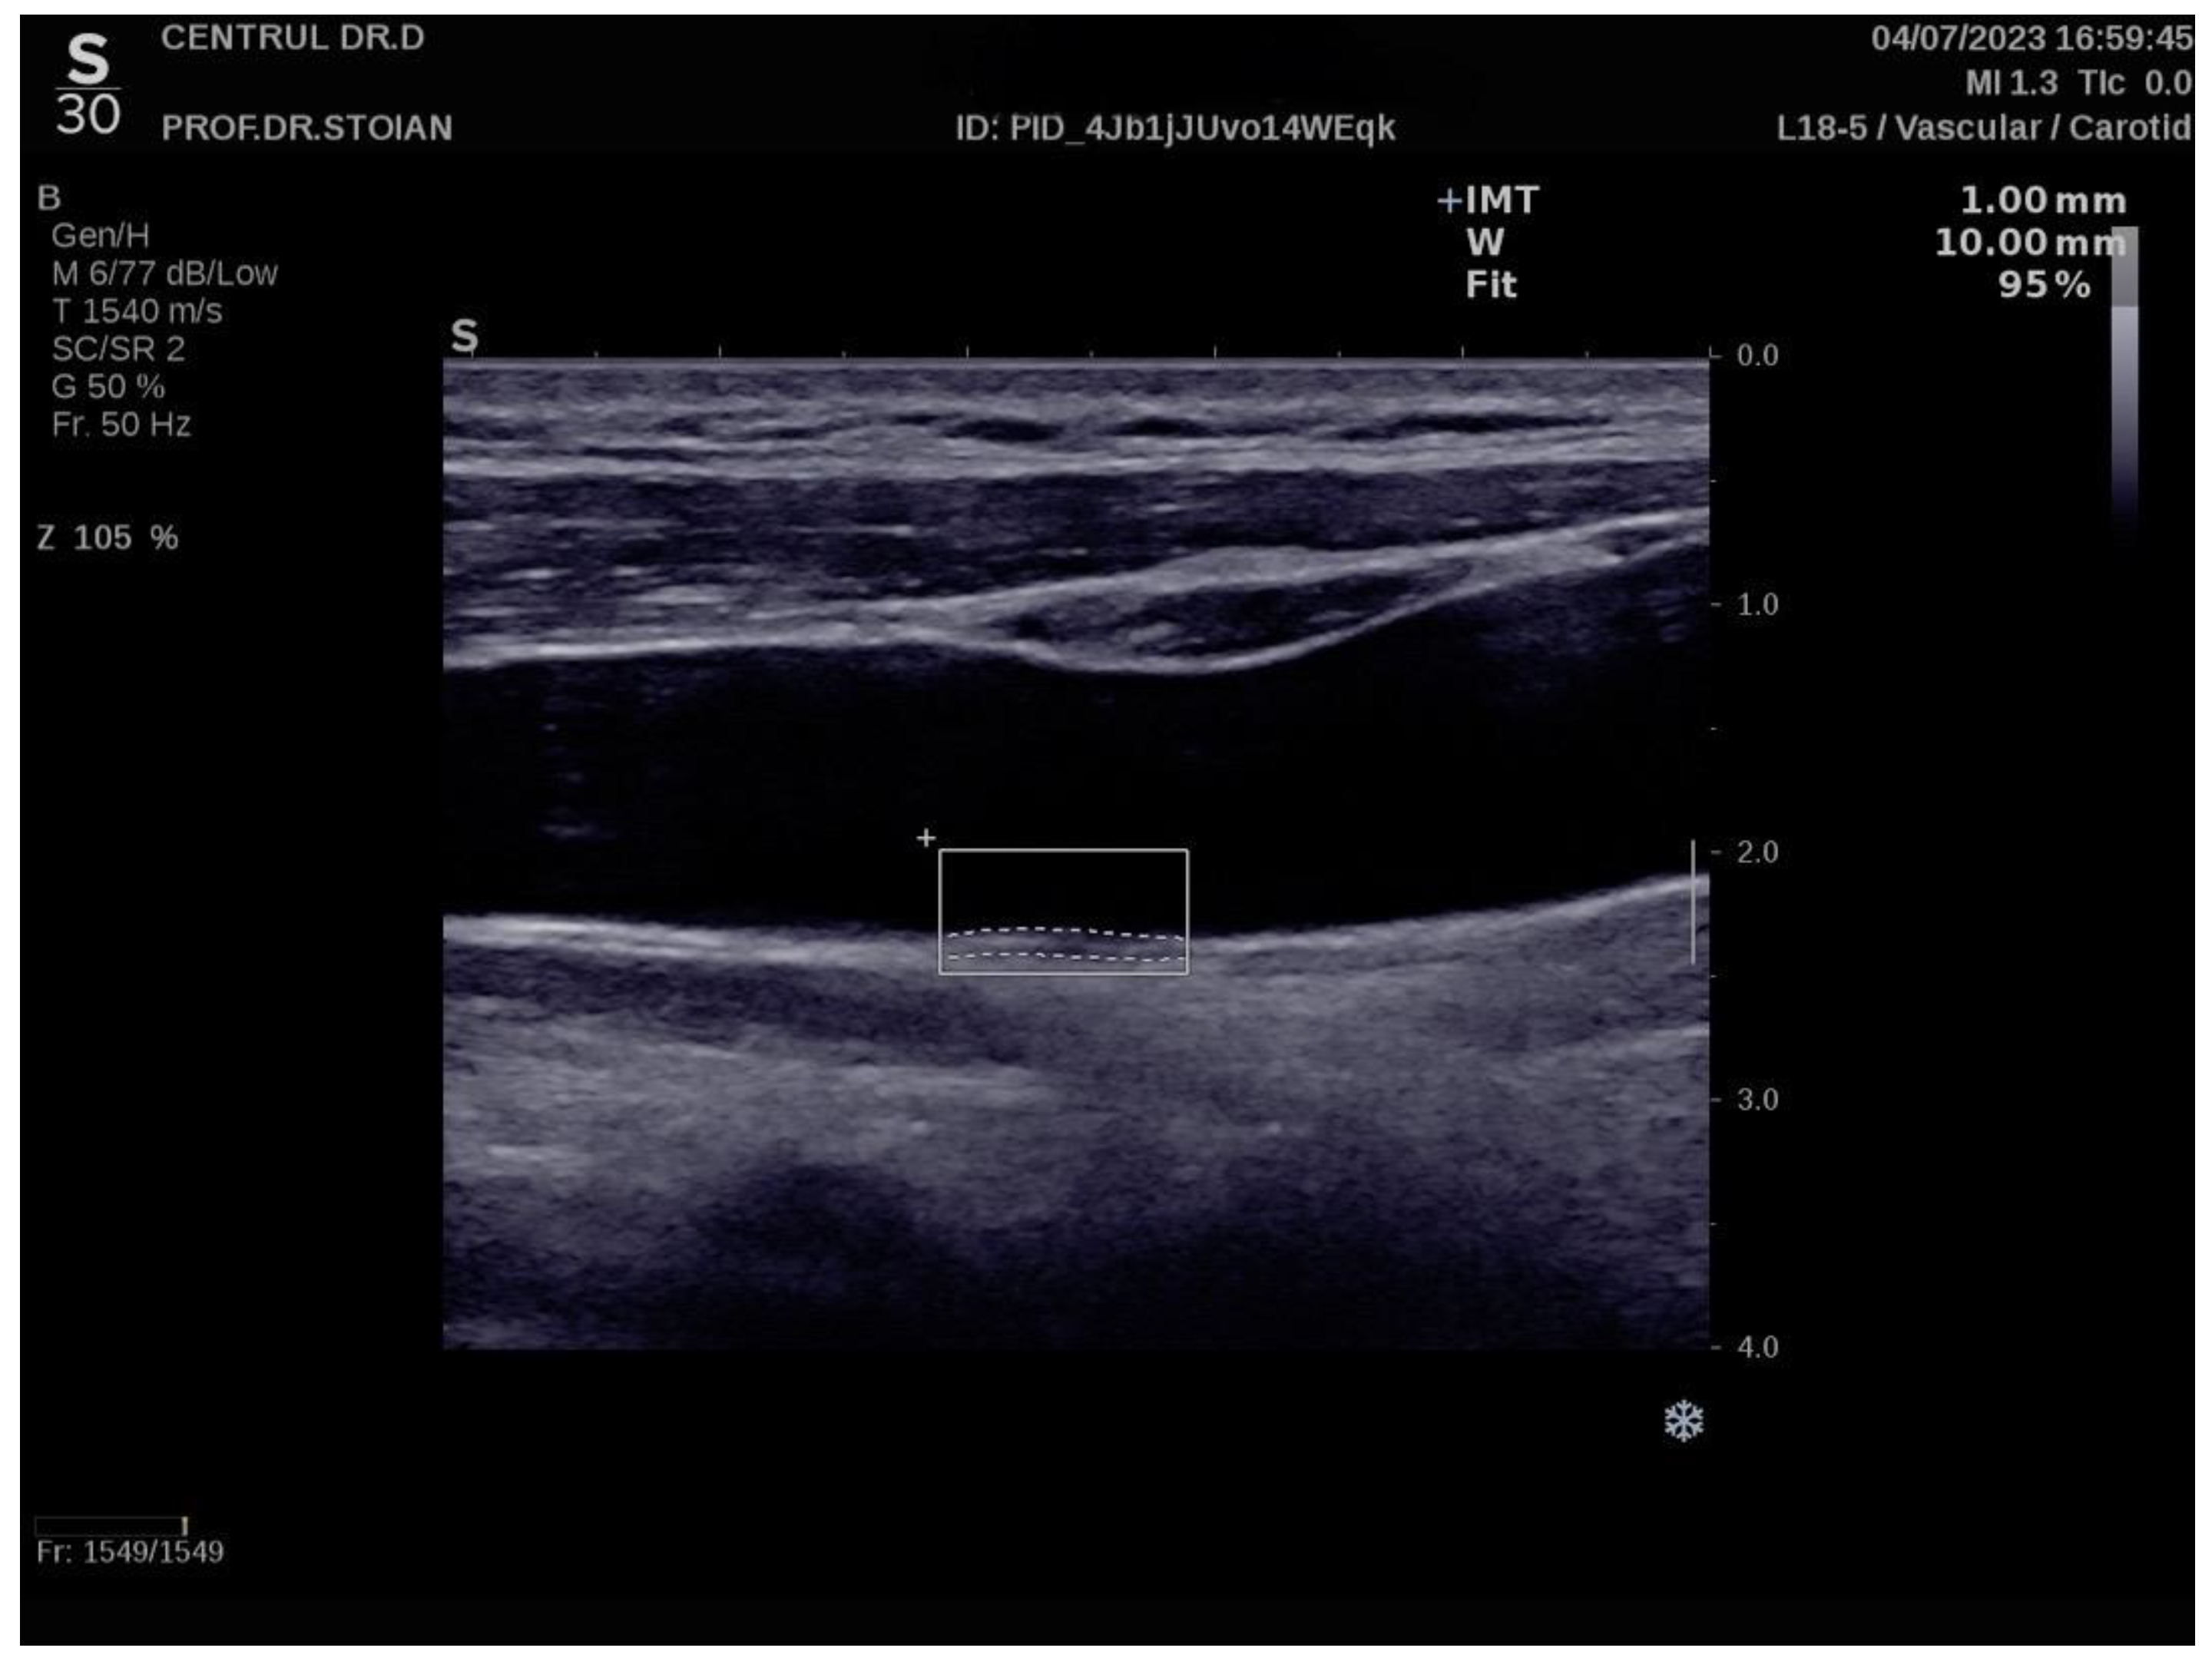

The Aixplorer MACH 30 ultrasound system (SuperSonic Imagine, Aix-en-Provence, France) was used to conduct an ultrasonographic assessment of carotid intima-media thickness. A certified and highly experienced sonographer conducted carotid ultrasonography on each participant included in the study. The procedure involved carefully positioning each subject to ensure optimal visualization of the carotid artery and applying a conductive gel to facilitate sound wave transmission. The sonographer then meticulously scanned the carotid arteries, using appropriate transducer settings based on individual anatomical characteristics, such as neck structure and adipose tissue distribution: SL 18-5 (5-18 MHz) or SL 10-2 (2-10 MHz). The CIMT values were automatically computed by the advanced software embedded within the ultrasound system (SuperSonic Imagine, Aix-en-Provence, France). This software analyzes the ultrasound images in real-time, providing precise measurements of the intima-media thickness without requiring manual calculation, ensuring both accuracy and efficiency in the evaluation process. The ultrasound images were captured during the end-diastolic phase, identified by the occurrence of the R wave on the electrocardiogram, ensuring consistency in arterial relaxation and minimizing variability in measurements [73]. For each participant, six separate CIMT measurements were taken, with three measurements performed on both the left and right carotid arteries. The measurements were carefully averaged to produce a mean CIMT value, which was subsequently used for analysis in the study. This approach helped to enhance the precision and reliability of the data by accounting for natural variations in arterial thickness across different locations and ensuring that the final CIMT value represented an accurate reflection of each patient's vascular status. To obtain optimal visualization of the right and left common carotid arteries, the subject is positioned in a supine position and instructed to extend their neck backward as far as comfortably possible, enhancing exposure of the cervical region. Additionally, the examiner carefully chooses the most suitable ultrasound transducer, ensuring the correct frequency range is used to maximize image clarity and resolution for accurate assessment of the CIMT. The scanning procedure begins with a transverse approach, starting at the clavicle and moving upward along the neck to identify the carotid bulb and the bifurcation of the common carotid artery into the internal and external carotid arteries. Once the carotid bulb is located, the examiner transitions to longitudinal scanning, allowing for a detailed assessment of the arterial walls and more precise measurement of the CIMT along the length of the artery. This systematic approach ensures thorough visualization of both the structure and flow characteristics within the carotid arteries. In this section, the carotid bulb is visualized on the left side of the ultrasound screen. Measurements are taken from the posterior wall of the carotid artery, specifically 1 to 2 cm distal to the carotid bulb. This location is chosen to avoid the geometrical irregularities of the bulb itself and to obtain accurate and consistent CIMT values from a more uniform segment of the arterial wall [74,75]. At end-diastole, the image is frozen, and the software automatically measures the CIMT in the examiner's selected region of interest, ensuring consistency and precision [76,77].

Figure 6 illustrates an example of CIMT evaluation for the left carotid artery obtained using this method in a normoweight subject, whose CIMT value falls within optimal limits. In contrast, Figure 7 depicts an elevated also left CIMT value of 1 mm, observed in a patient with grade II obesity. It is important to note that personal data of the evaluated subjects are not displayed to ensure confidentiality.

Figure. Example of a high value of left CIMT measurement in a subject with obesity grade II using the Aixplorer MACH 30 ultrasound system.

Preprints 147944 g002